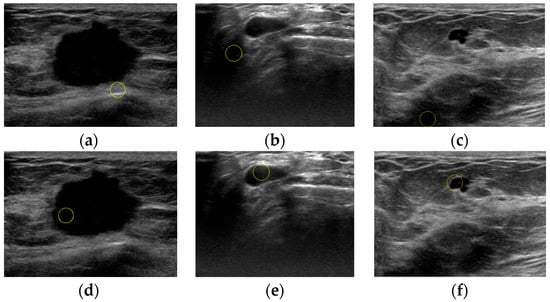

An Automatic Localization Algorithm for Ultrasound Breast Tumors Based on Human Visual Mechanism